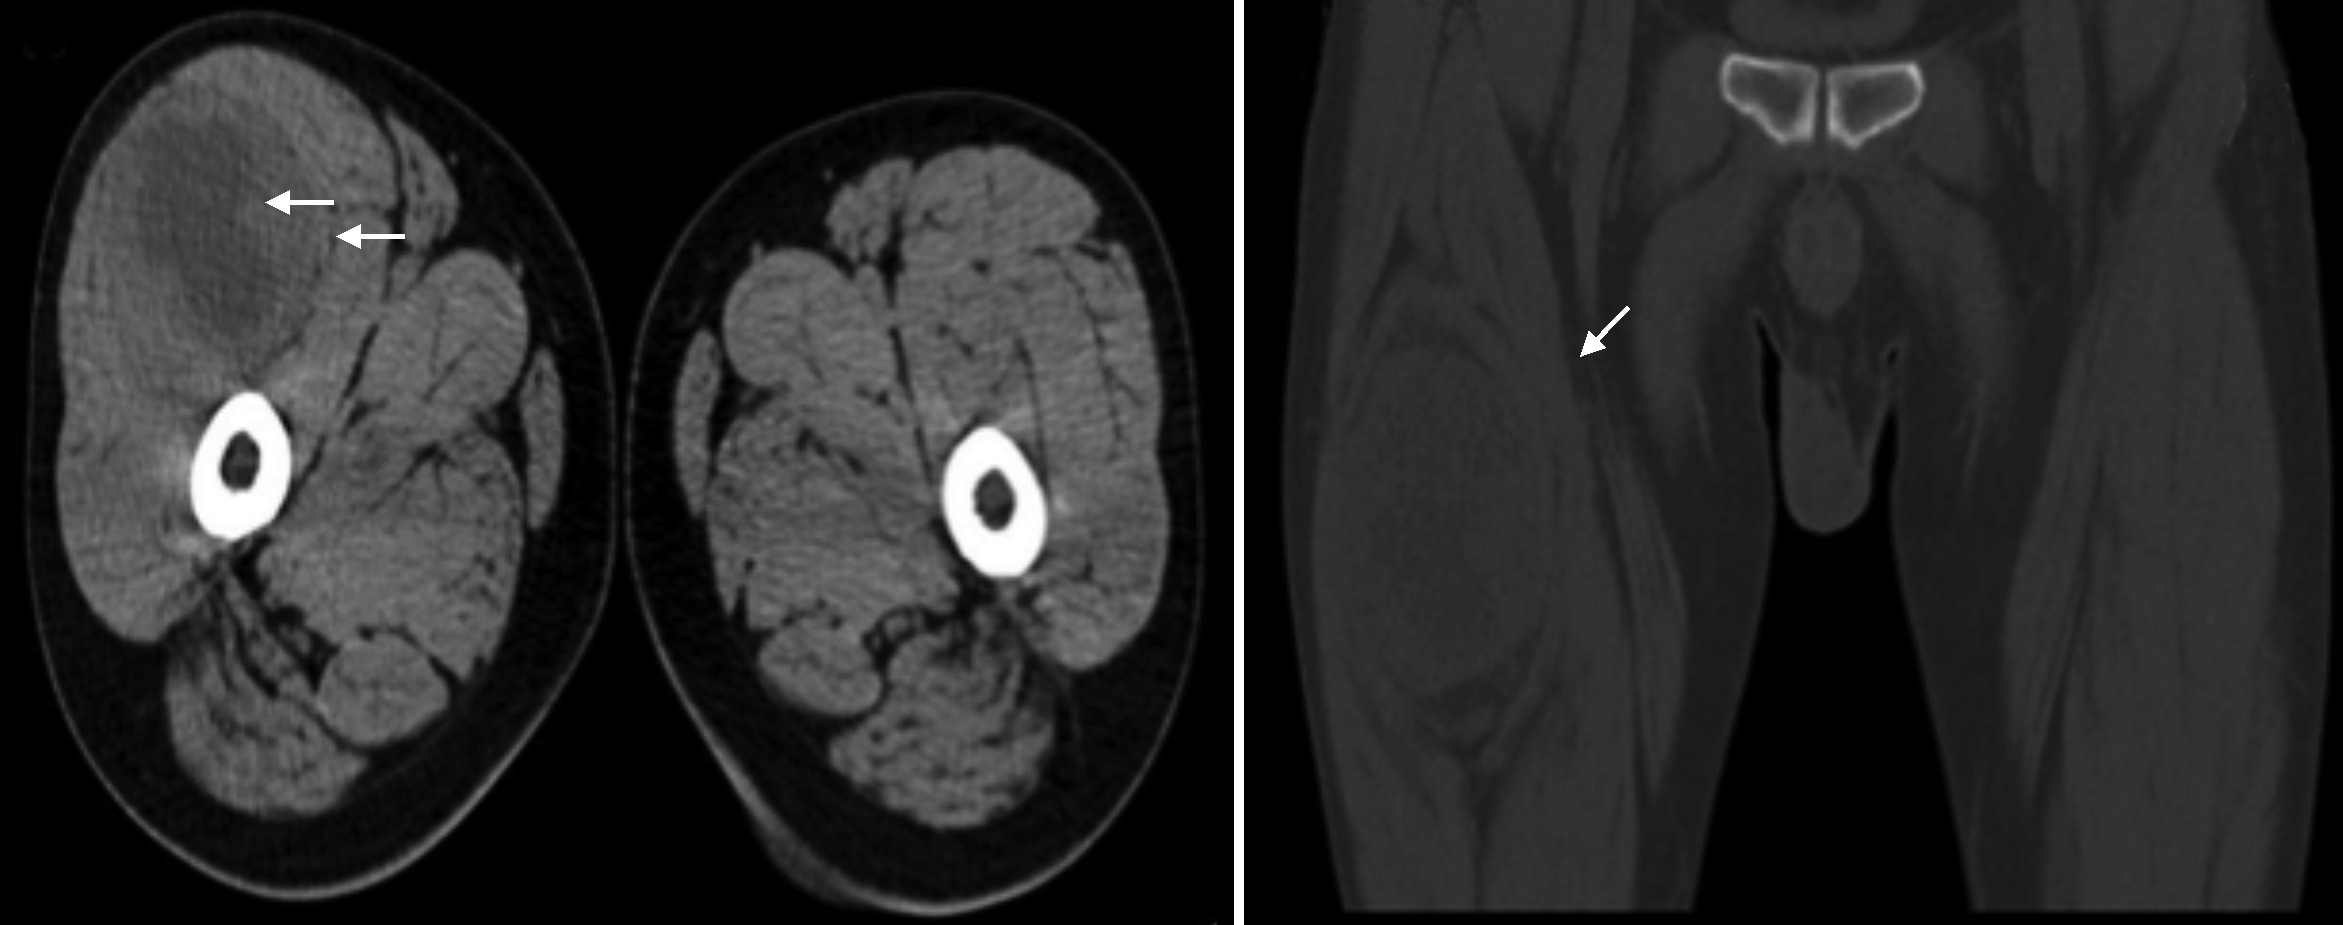

实验室检查结果:血常规检测显示白细胞计数6.57×109/L,血红蛋白170 g/L,血小板计数275×109/L,中性粒细胞39×109/L,淋巴细胞3.22×109/L。凝血酶原时间11.6 s,纤维蛋白原1.5 g/L。天门冬氨酸氨基转移酶41.5 μmol/(min·L),总胆红素16.9 μmol/L,清蛋白46.9 g/L,球蛋白28 g/L,碳酸氢根22.92 mmol/L,r谷氨酰转肽酶219.08 μmol/(min·L),总胆汁酸18 μmol/L。传染病筛查、乙肝五项检测未见明显异常。超声检查发现右侧大腿前侧上段肌层内见大小约10.0 cm×5.8 cm×9.0 cm囊实性包块,形态规则,边界欠清,内部回声不均,以囊性为主,彩色多普勒血流成像(color Doppler flow image,CDFI)显示其内棒状血流信号。脉冲多普勒宽度(pulse width,PW)检查示PSV为22.6 cm/s, 阻力指数为0.68,提示右大腿前侧上段囊实性包块,以囊性为主,良性病变可能性大(图1)。下肢CT平扫检查见右侧股前部肌肉间团块状软组织密度影,边界尚清,中心层面大小约6.5 cm×6.3 cm×8.2 cm,病灶内密度欠均匀,见片状稍低密度影,邻近肌肉及骨质未受侵(图2)。患者术中切除物行术后常规组织病理学检查行苏木精伊红染色(右大腿)梭形细胞肿瘤伴出血坏死,免疫组织化学染色示CD57(+),CD34(-),S100(+),Desmin(-),CK(-),Vimentin(+),BCL-2(+),Ki-67(1%+)。送检组织界限清楚,其内见成片梭形细胞,异型性不明显,病理性核分裂像<1个/50 HPF,部分区域见组织坏死,组织中见多个巨大菊形团结构,菊形团中央见胶原形成。

由于LGFMS较罕见,临床表现和影像学特征缺乏特异性,故诊断具有一定的困难。本例患者主要表现为右大腿生长缓慢的无痛性包块,病程较长,患者及时就诊意识不足。但是在入院后的相关检查中发现,该肿瘤在超声检查影像中主要表现为巨大囊实性包块,内部回声不均,以囊性为主,CDFI检查其内见点棒状血流信号,阻力指数<0.7,与以往报道的LGFMS为低回声实性包块,部分呈分叶状,回声均质或不均质,多低于肌肉回声,其内可见血流信号,血流频谱表现为低速高阻特点的声像图表现不相符[7, 8, 9];CT影像则表现为右侧股前部肌肉间见团块状软组织密度影,考虑为血管瘤或畸胎瘤可能,二者影像学结合多倾向右大腿良性病变。超声引导下包块细针穿刺活检中,由于包块囊性成分较多,细针穿刺检查获取的组织细胞相对较少,故误诊为囊肿。本例的诊断过程提醒我们,在今后工作中应对可疑病变选择进一步的增强影像学检查,采用空芯针代替细针穿刺以提高活检阳性率,提高诊断的准确性。

LGFMS最终的确诊依赖术后切除物的病理学检查及免疫组织化学染色,但术前影像学检查对手术仍有一定的指导作用。超声检查对于肿瘤的囊实性成分及血供情况的判断以及有无淋巴结转移有较好的特异性,而CT及MRI可以直观地描述病变的形态、结构特征以及与周围组织的关系[10],影像学检查可在这些不典型病例的诊疗过程中提供有价值的信息,影像医师在今后的工作可以提高对本病的认识。